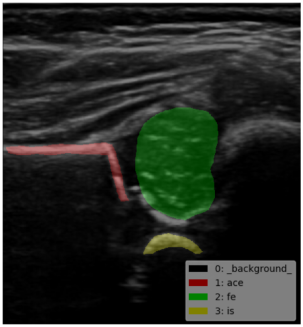

这个指标真是厉害了啊,AP50和AP75竟然都是1。。。看一下结果吧,,

classes = ['__background__', 'ace','fe','is']

看一下效果啦: